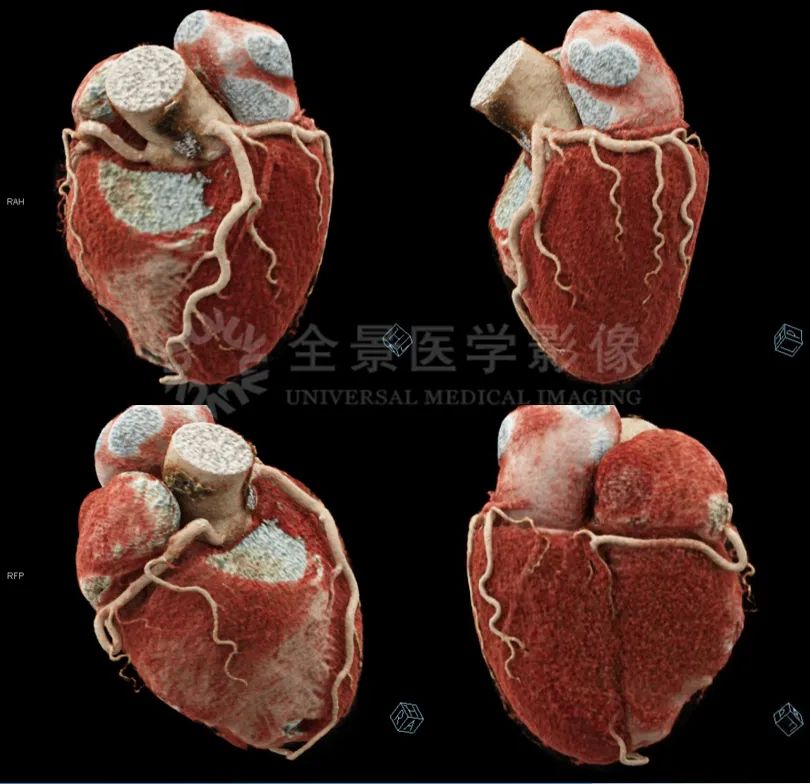

2.能够更加真实地显示血管情况,有助于心脑血管疾病的筛查、诊治及术后随访。

正常冠脉,cVRT表现

冠心病PCI术后,左回旋支近中段支架通畅、形态正常。